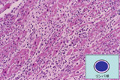

- ★(3)Viral myocarditis

Macroscopic view (fulminant viral myocarditis): There are multiple patchy, discolored areas as well as striking edema of the myocardium demonstrated by a reddish appearance and soft consistency.